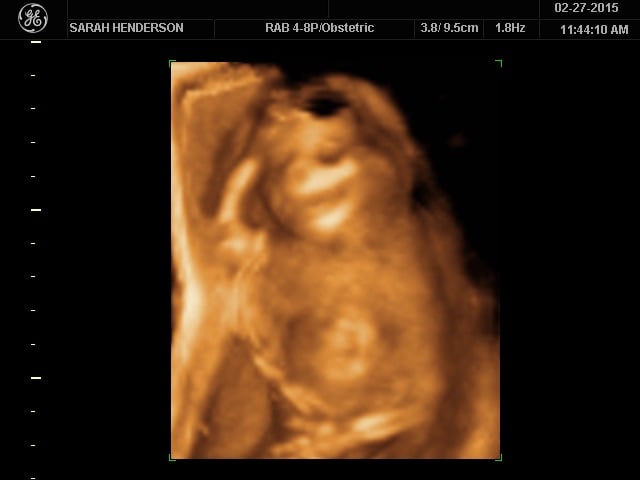

ok so I may be being a bit of an attention whore considering I've posted on two different threads, but I wanted more people to see it.. I found out the gender today, ITS A GIRL!!! I've never felt so happy in my life, it's such an amazing feeling! I've known it was a girl since the day I found out but no one believed me lol.. My beautiful Leighton Skye Henderson! Now I can start shopping & decorate the nursery!